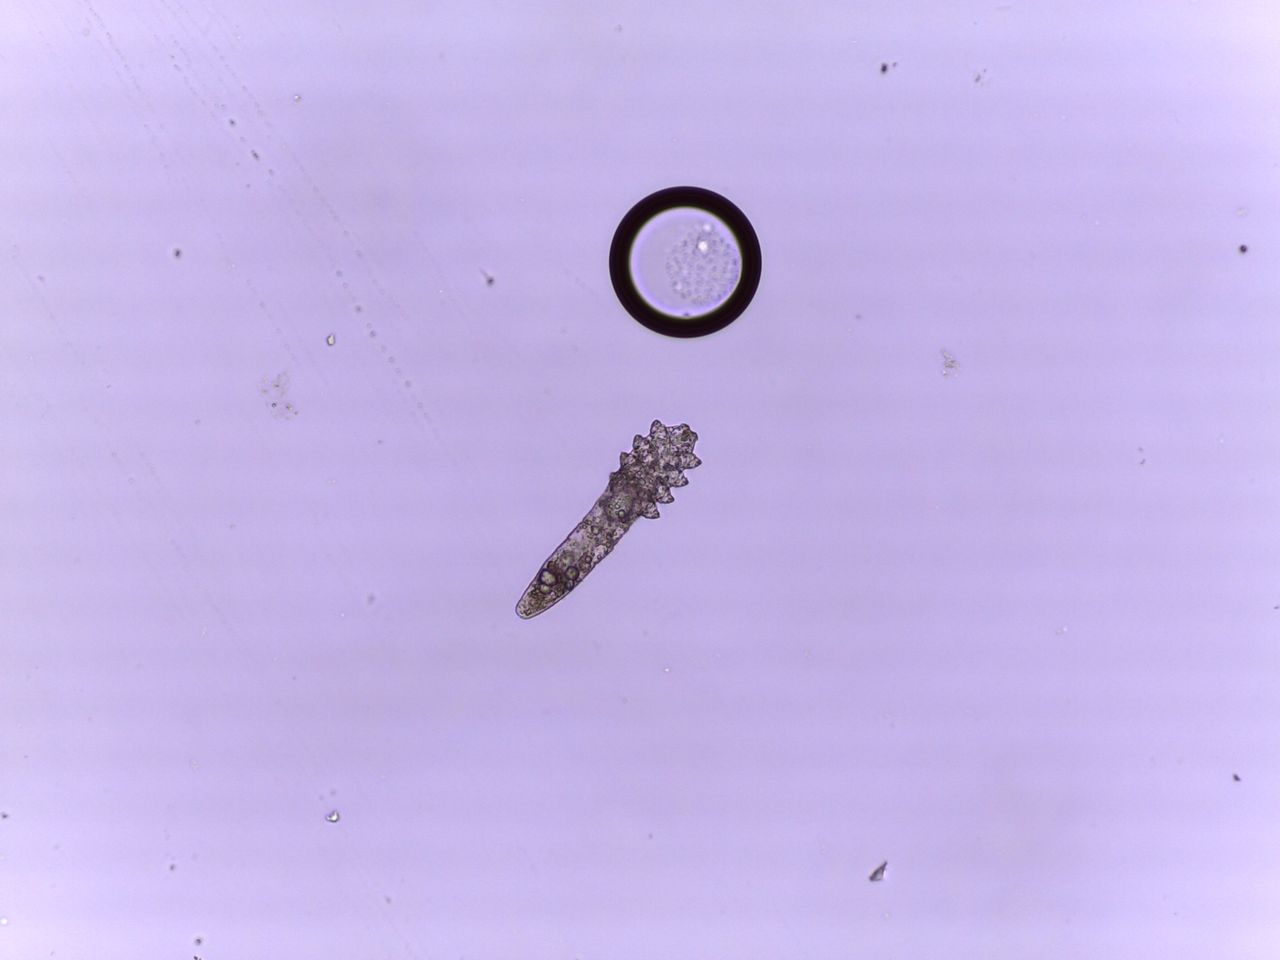

- micosi (esame micologico microscopico diretto)